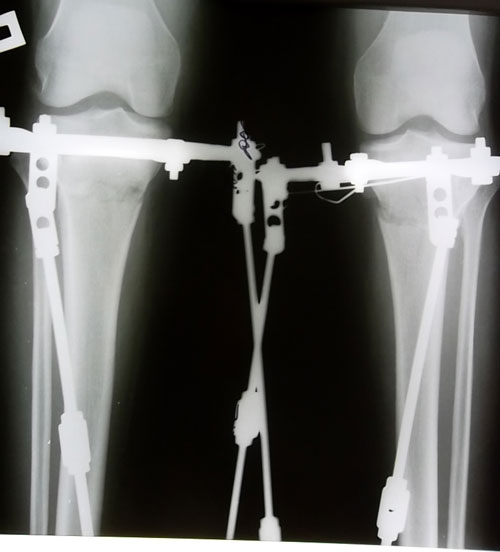

Рентгеновские снимки до операции.

SAM_3428.JPG

прямая проекция

SAM_3429.JPG

боковая проекция